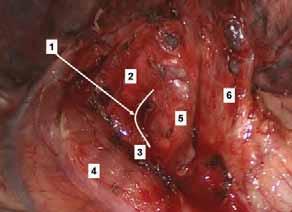

Rycina 70.7.

Rycina 70.8.